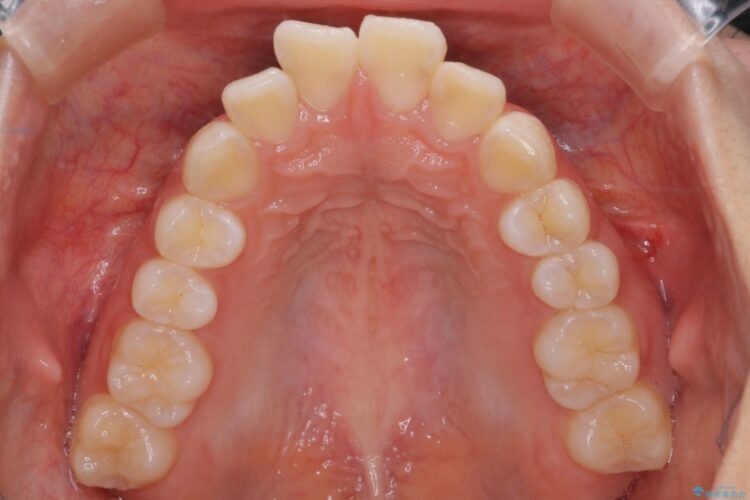

前歯のガつきと口元が出ていることを気にされご来院された患者様です。

上下4番目の歯を抜歯してガタつきを改善しながら口元を下げる治療計画を立てました。